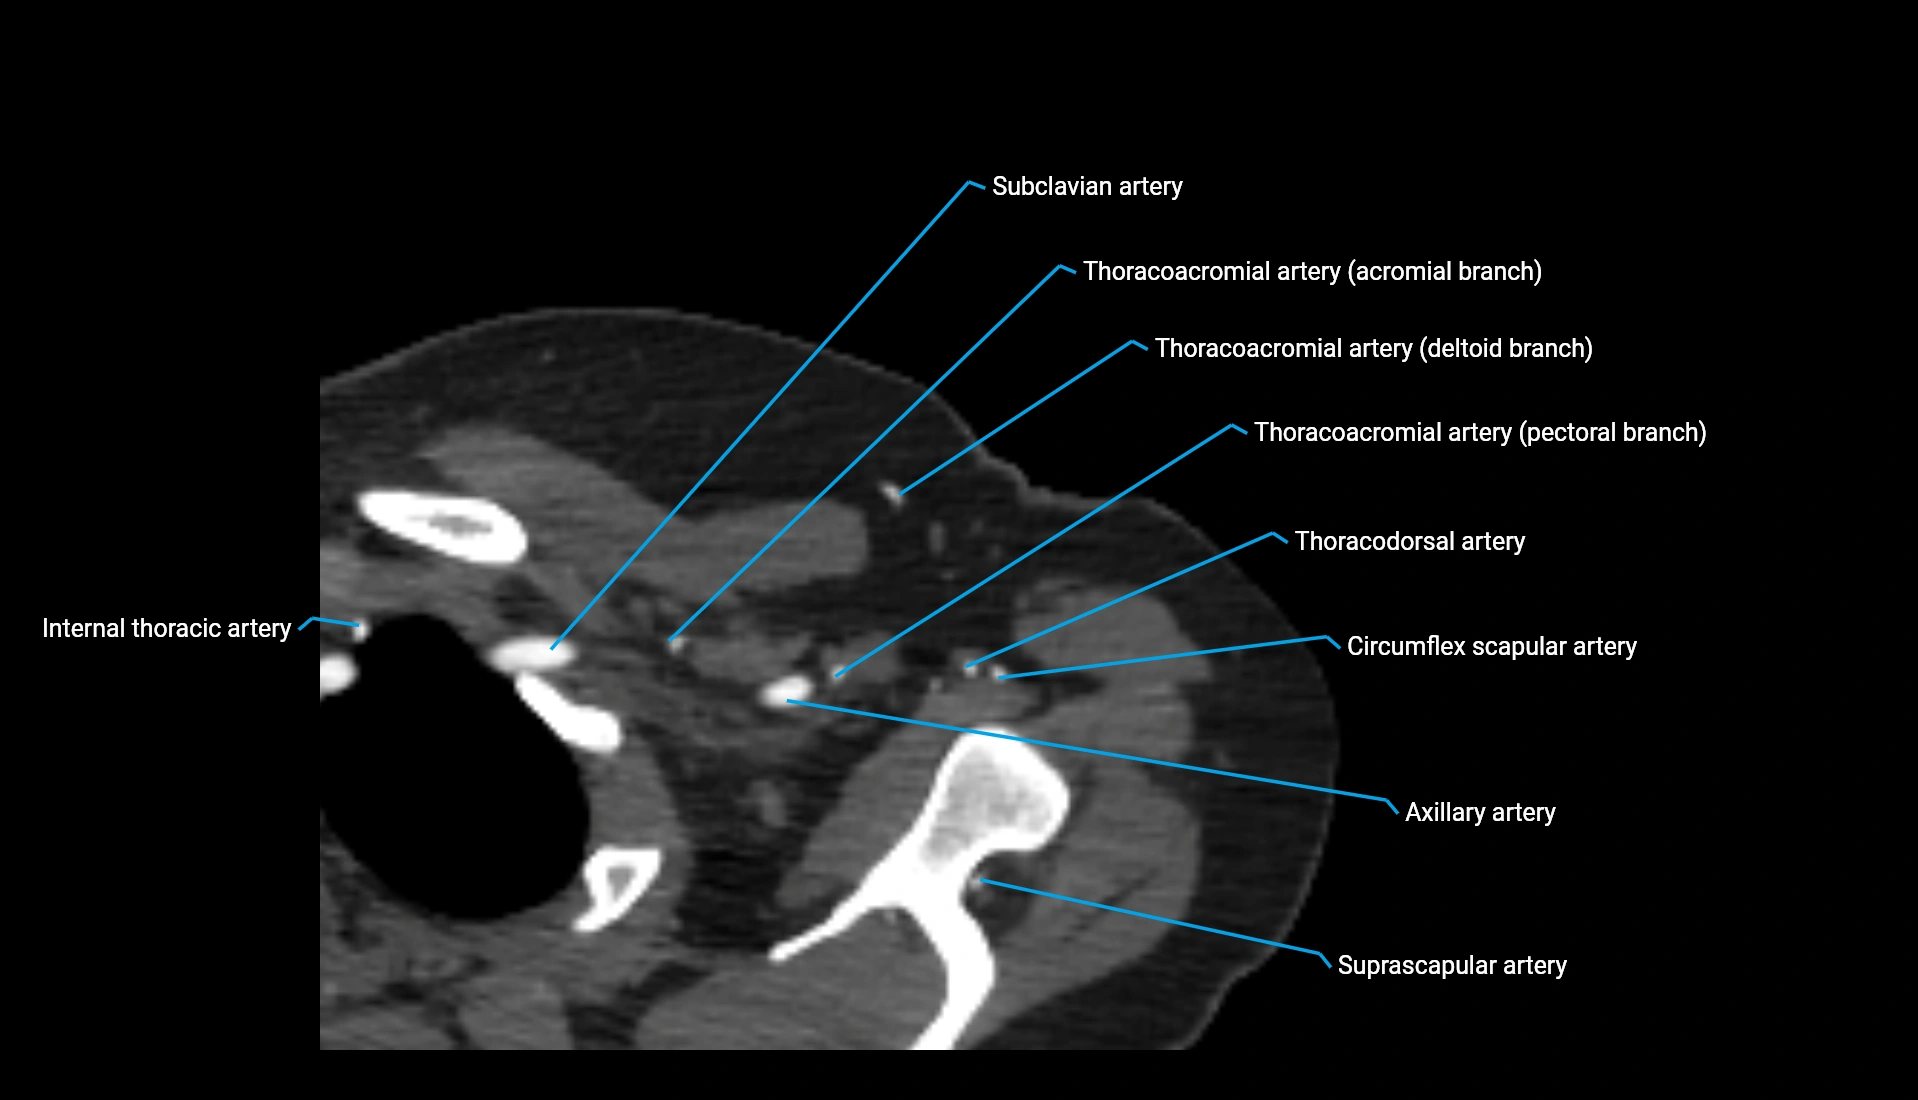

CT Appearance

Post-Contrast CT:

• Bone: No enhancement

• Joint capsule and synovium: Mild enhancement outlining the joint

• Improves contrast between soft tissues and bony margins

• Useful in detecting subtle joint abnormalities or postoperative changes